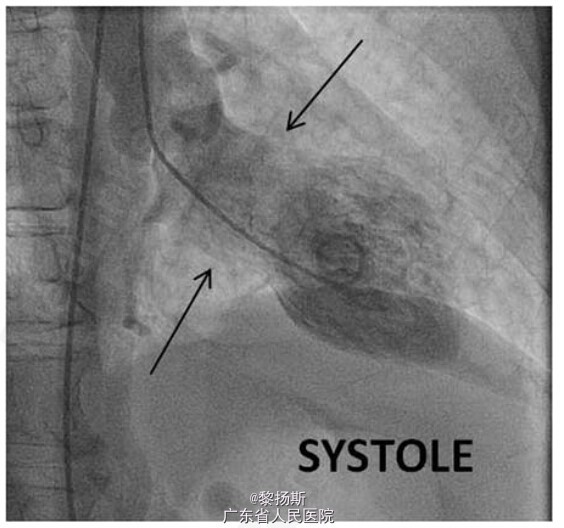

诊断考虑章鱼壶心肌病(图1)。立即予阿司匹林 162mg 和普拉格雷 60mg,且送至导管室检查。造影可见冠脉管腔不规则,属于非阻塞性冠脉疾病(见图 5 和 6)。左心室造影图显示 EF 值为 35%,心尖运动失能,而基底段运动过度(见图 7 和 8)。